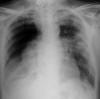

Fibrosis pulmonar. ICC.

Cardiomegalia. ICC.

EAP